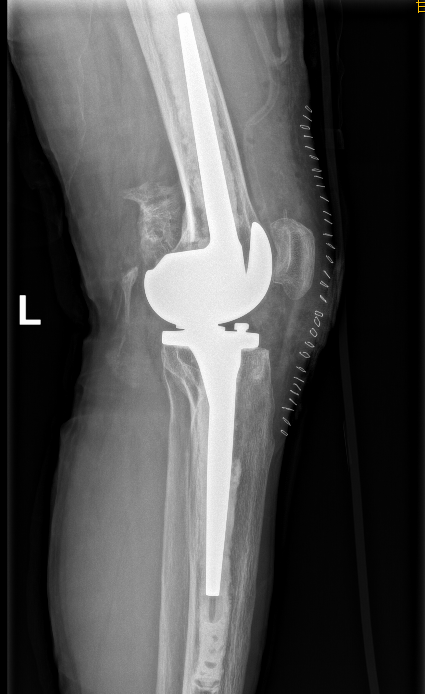

在确定治疗方案后,张主任团队立即实施手术,为患者进行旋转铰链膝关节置换术,该手术技术含量高、难度大,对医师的技术水平和临床经验有更高的要求,为成人导航 首例。

历经2.5小时,这项高难度的4级手术顺利完成。术后患者恢复良好,疼痛明显缓解,关节屈曲得到极大改善,第3天小林自行下床行走,脸上露出了久违的笑容,为张海军主任团队精湛的医疗水平竖起了大拇指。手术的成功开展不仅从根本上解除了患者病痛,而且改善患者生活质量。

张海军主任指出旋转铰链膝关节置换术不仅能保证膝关节的前后屈伸运动,而且更接近正常膝关节的运动能力。该技术需要手术医生对膝关节疾病诊治有较深的造诣,不仅要熟练掌握膝关节置换术的多种方法,而且要了解国内外的最新技术动态,是一项高难度手术。